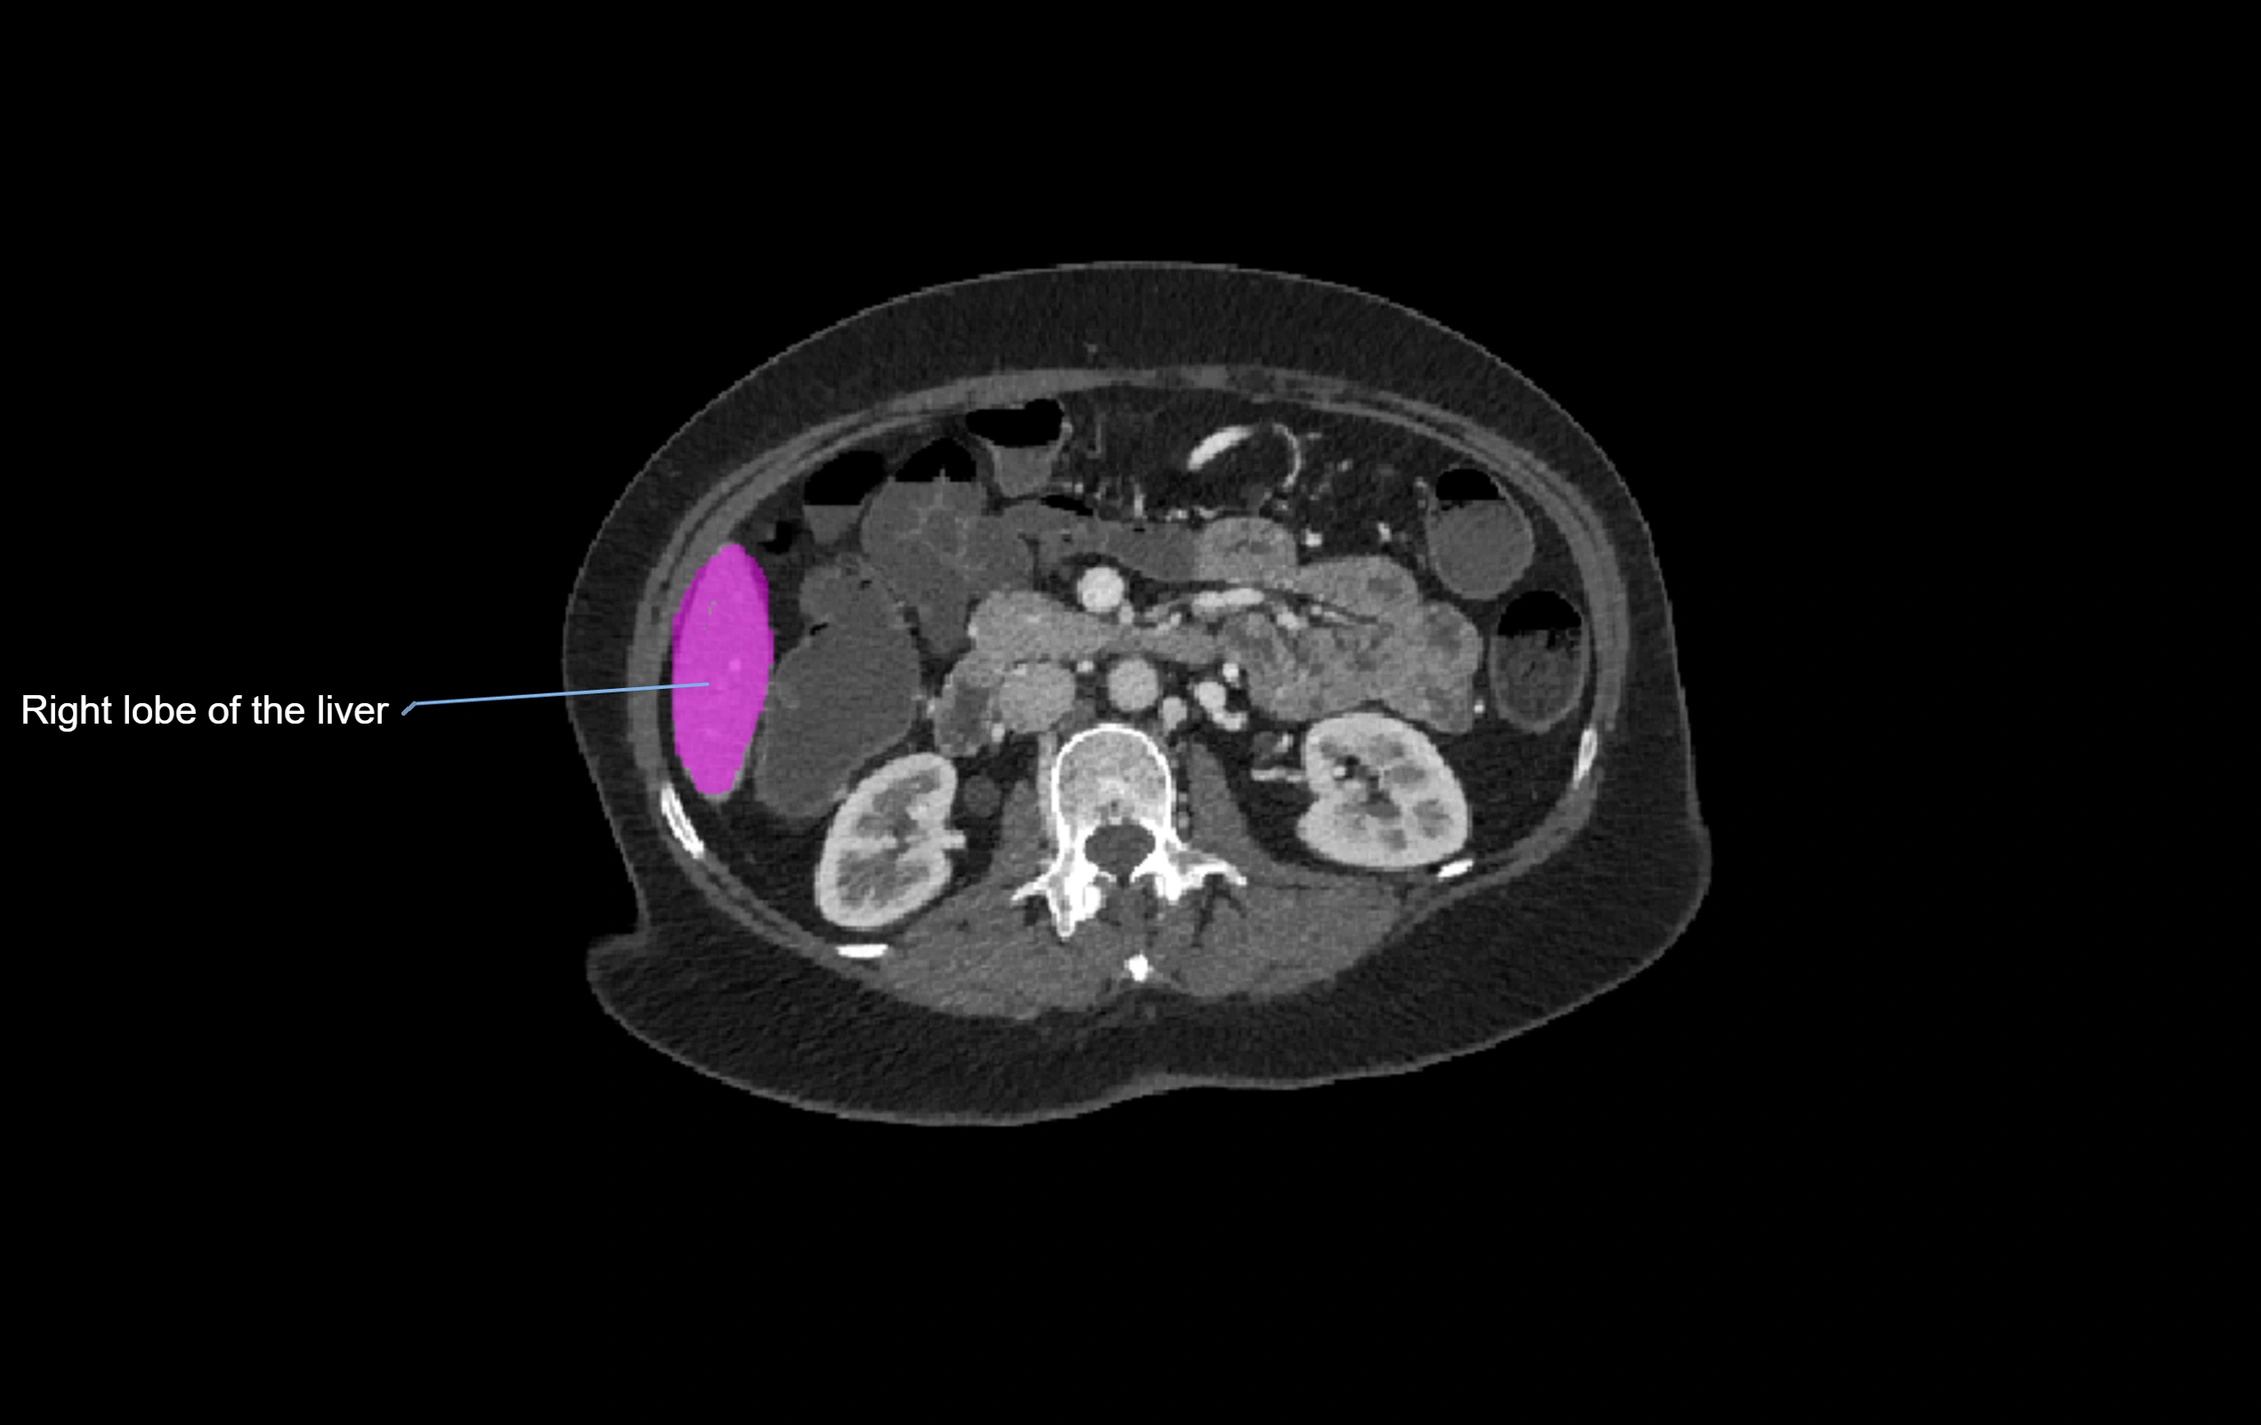

CT Image

image